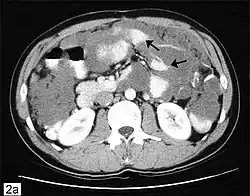

CT scanning is preferred to assess the extent of the tumor in the abdominopelvic cavity, though magnetic resonance imaging can also be used.[28] CT scanning can also be useful for finding omental caking or differentiating fluid from solid tumor in the abdomen, especially in low malignant potential tumors. However, it may not detect smaller tumors. Sometimes, a chest x-ray is used to detect metastases in the chest or pleural effusion. Another test for metastatic disease, though it is infrequently used, is a barium enema, which can show if the rectosigmoid colon is involved in the disease. Positron emission tomography, bone scans, and paracentesis are of limited use; in fact, paracentesis can cause metastases to form at the needle insertion site and may not provide useful results.[29] However, paracentesis can be used in cases where there is no pelvic mass and ascites is still present.[29] A physician suspecting ovarian cancer may also perform mammography or an endometrial biopsy (in the case of abnormal bleeding) to assess the possibility of breast malignancies and endometrial malignancy, respectively. Vaginal ultrasonography is often the first-line imaging study performed when an adnexal mass is found. Several characteristics of an adnexal mass indicate ovarian malignancy; they usually are solid, irregular, multilocular, and/or large; and they typically have papillary features, central vessels, and/or irregular internal septations.[31] However, SCST has no definitive characteristics on radiographic study.[32]

In advanced cancers, where complete removal is not an option, as much tumor as possible is removed in a procedure called debulking surgery. This surgery is not always successful, and is less likely to be successful in women with extensive metastases in the peritoneum, stage- IV disease, cancer in the transverse fissure of the liver, mesentery, or diaphragm, and large areas of ascites. Debulking surgery has usually only been done once[28] but a recent study has shown a longer overall survival in recurrent ovarian cancer when surgery combined with chemotherapy was performed compared to treatment with chemotherapy alone.[100] Computed tomography (abdominal CT) is often used to assess if primary debulking surgery is possible, but low certainty evidence also suggests fluorodeoxyglucose‐18 (FDG) PET/CT and MRI may be useful as an addition for assessing macroscopic incomplete debulking.[101] More complete debulking is associated with better outcomes: women with no macroscopic evidence of disease after debulking have a median survival of 39 months, as opposed to 17 months with less complete surgery.[26] By removing metastases, many cells that are resistant to chemotherapy are removed, and any clumps of cells that have died are also removed. This allows chemotherapy to better reach the remaining cancer cells, which are more likely to be fast-growing and therefore chemosensitive.[29]